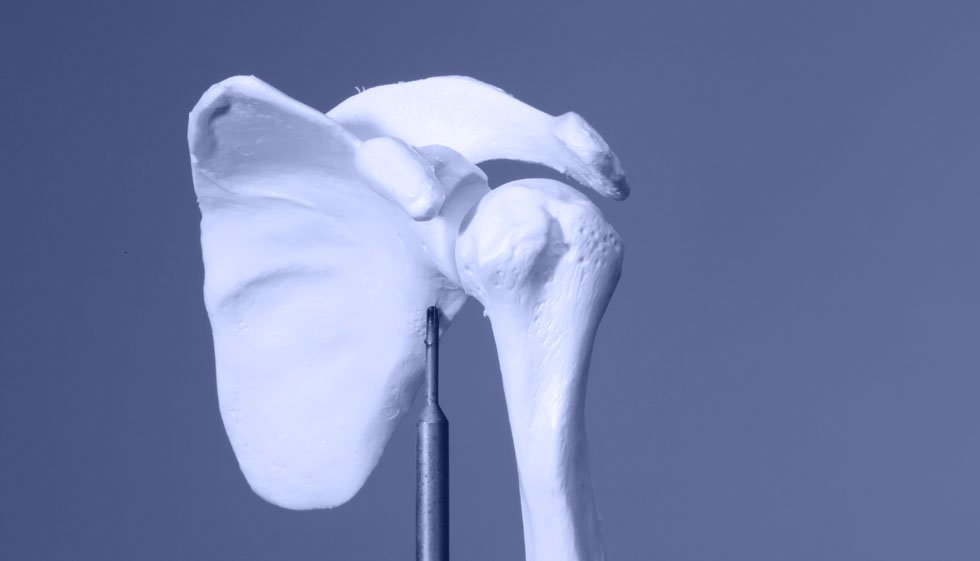

Schulterschmerzen behandeln wir in Köln mit ärztlichen und physiotherapeutischen Therapieverfahren. Die Schulter besteht aus Schulterblatt, Schulter Haupt- und Schulter Eck- Gelenk. Das Gelenk zwischen Brustbein und Schlüsselbein gehört funktionell ebenfalls mit zur Schulter.

Die Schulter bildet ihr Schultergelenk aus einer großen Gelenkkugel und einer kleinen Gelenkpfanne. Die Gelenkpfanne der Schulter wurde im Laufe der Evolution soweit verkleinert bis der heutige Bewegungsumfang entstanden ist. Möglich wurde das erst durch besondere Bänder, die die Kapsel des Schultergelenkes passiv verstärken, Glenohumerale Bänder, und der Rotatorenmanschette, einer Gruppe von Muskeln, die das Schultergelenk aktiv stabilisieren.